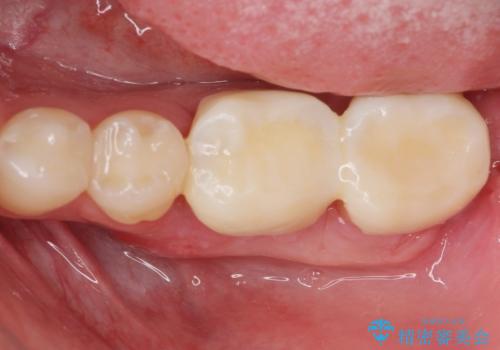

- APF 16.5万円 セラミックインレー 7.7万円×2費用は治療当時の料金となります

治療後の写真は2週間後の写真です。歯茎の治癒が完全に治るのは半年くらいかかるので半年後に最終的な被せ物を入れる予定です。